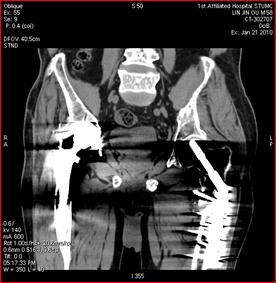

傳統(tǒng)CT成像,未顯示病灶 40keV單能量下診斷病灶

高能量X射線可以去除高密度金屬引起的偽影

常規(guī)CT 寶石能譜CT

140keV能量成像可以除去金屬引起的偽影,更加清晰觀察術(shù)后情況